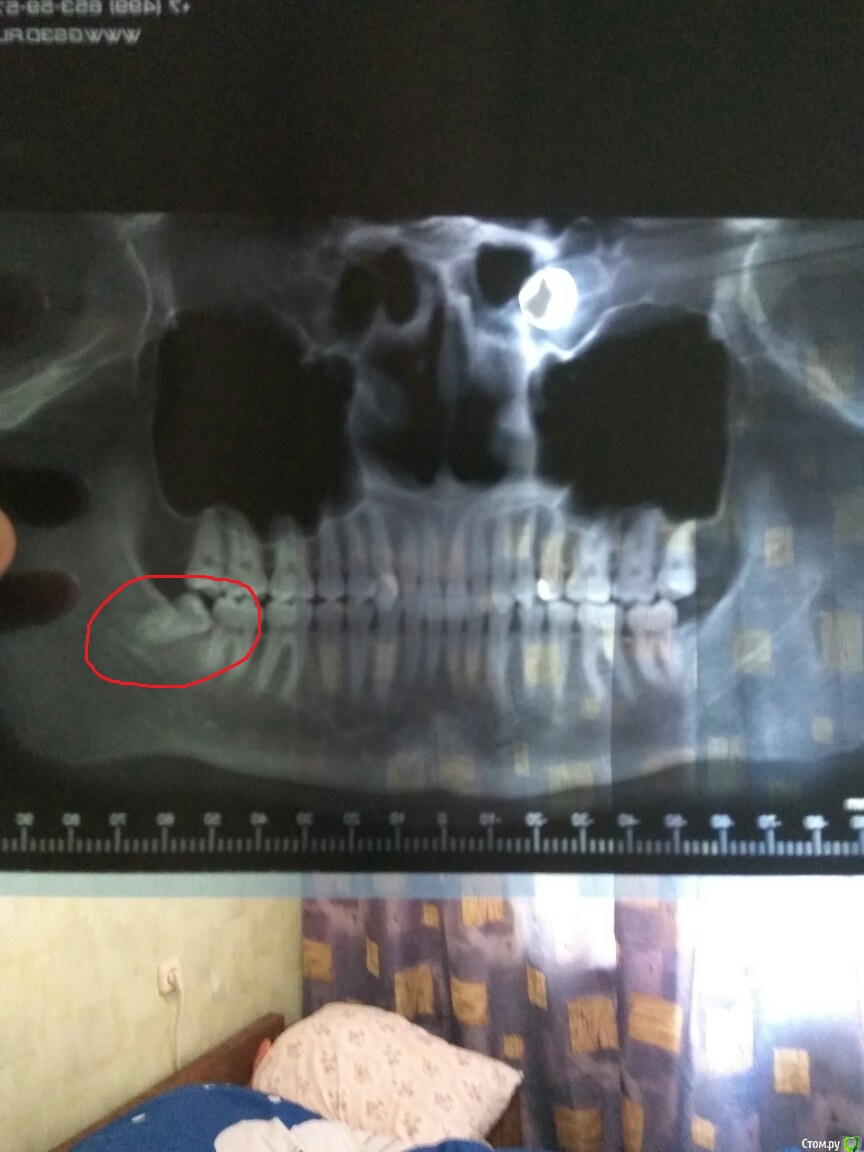

Recycler667 Опубликовано 17 августа, 2019 Поделиться Опубликовано 17 августа, 2019 (изменено) Доброго времени суток, 13.08.2019 я удалил зуб мудрости, операция прошла быстро и без боли, после того как наркоз отошел боль была, несколько часов очень сильная, потом терпимо. С каждым днем становилось лучше, но 16.08.2019 я пошел делать рентген на наличие осколков, на всякий случай, и был не приятно удивлен тем что он там оказался. Врач сказал что он либо инкапсулируется в челюсти и все будет в порядке, либо воспалится и его придется удалять, но то был другой врач, тот который проводил операцию на данный момент ушел в отпуск( Да и поликлиника государственная, очереди, все торопятся, и толком я не понял что и как( На момент удаления этот зуб мудрости не болел, не воняло из-за рта и он был целым, не гнилым, удалил - потому что он не правильно шел, в горло и мешал дышать! А так же убивал корни семерки! Сразу хочу сказать что я бедный, и на данный момент без работы, денег нету порой даже на еду, не то что на операции, поэтому я пошел в бесплатную. На панарамный снимок полторы тысячи рублей еле нашел( На данный момент - боль испытываю только если максимально широко раскрываю рот, либо если задеваю нитки шва. Температуры не было, опухания тоже, если долго говорю или жую - может немного начать поддергивать примерно то место где на снимке видно этот самый осколок, то-ли корня, то-ли самого зуба. Прошу дать мне совет, куда обращаться, я так понимаю что в челюстную хирургию уже? И стоит ли? Ужасно не хочу больше никаких операций! Есть ли хотя бы какая-то надежда что он сам выйдет, или без последствий его можно оставить там? Заранее выражаю огромную благодарность всем ответившим, и желаю здоровья! Прошу прощения за плохое качество фото, надеюсь понятно. Изменено 17 августа, 2019 пользователем Recycler667 1 Ссылка на комментарий